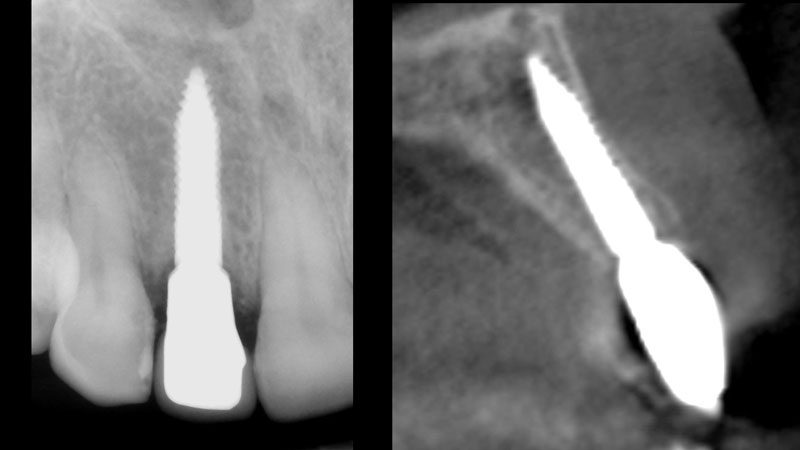

Hình 1. Hình ảnh răng cửa bên hàm trên bị gãy sâu dưới nướu, chú ý khoảng cách chiều ngang (gần – xa) đo được trên phim quanh chóp.

Hình 19. Phim quanh chóp và CBCT sau 3 tháng gắn phục hình.